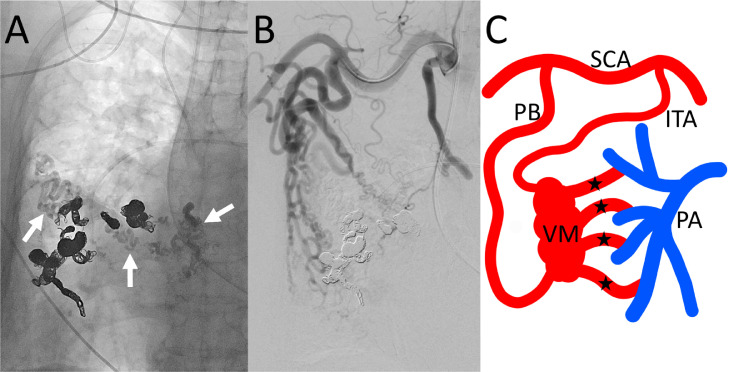

Fig. 3.

Radiograph and angiography after embolization of systemic artery-to-pulmonary artery (PA) vascular malformation (VM) of the right chest wall. (A) Radiograph shows coils placed in drainers and N-butyl cyanoacrylate cast (arrows) injected from the internal thoracic artery and the pectoral branch. (B) Angiography of the right subclavian artery shows decreased enhancement of the VM. (C) Schematic drawing of the embolization procedure. Main drainers (stars) of VM were connected to segmental PAs. These drainers were embolized to coils through the segmental PAs. Then, N-butyl cyanoacrylate mixed with iodized oil was injected from the 2 main feeders: internal thoracic artery and pectoral branch.

ITA, internal thoracic artery; PA, pulmonary artery; PB, pectoral branch; SCA, subclavian artery; VM, vascular malformation.